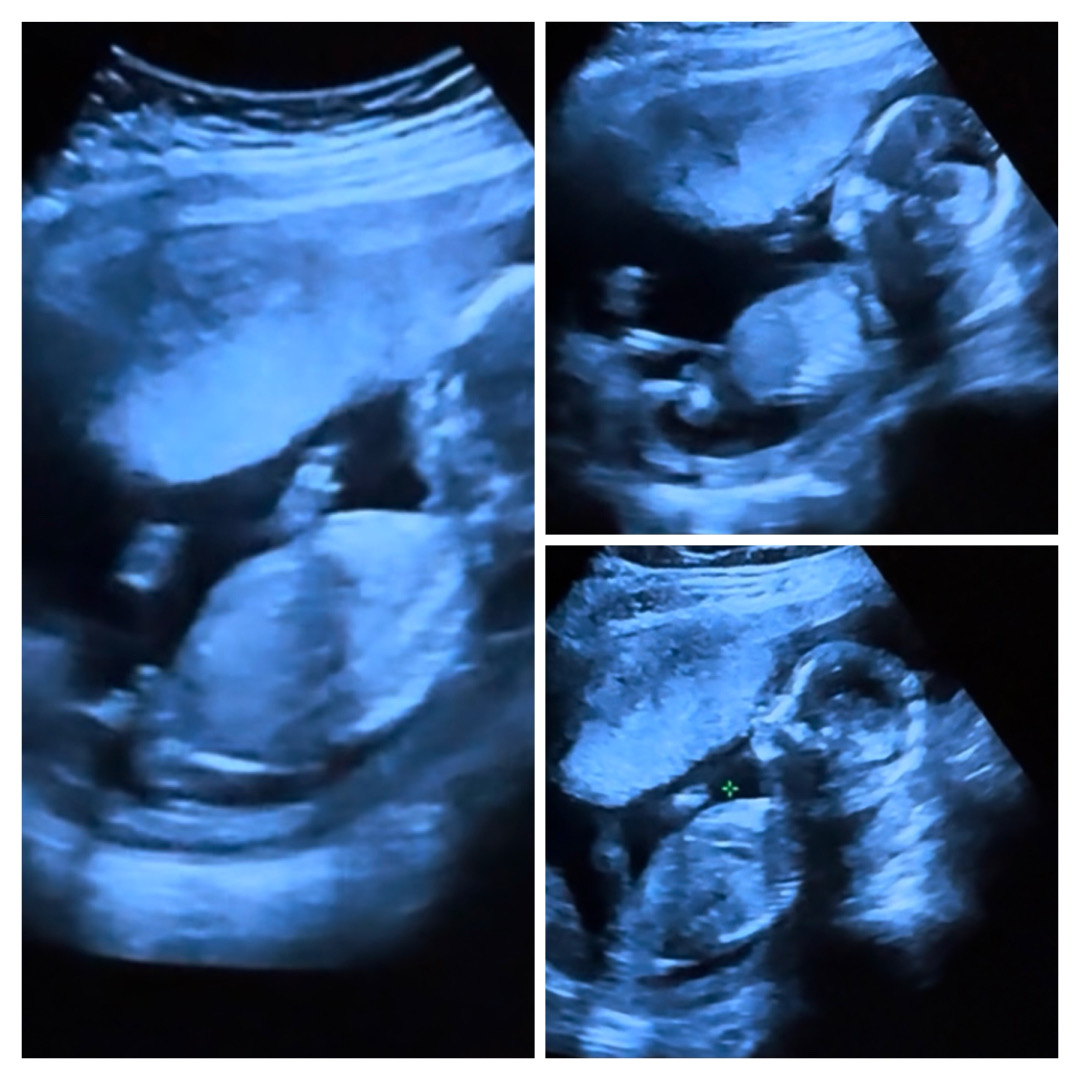

성별?!?! 어떤것 같으시나요

16주인데 캡쳐를 잘 한건지도 모르겠지만 딸… 같은데 어떻게 보이세요?

아들 이요. 제 아이와 비슷한데 전 아들 확정이요🌶

저도 아들에 한표요

아들같아요!

아들한표용